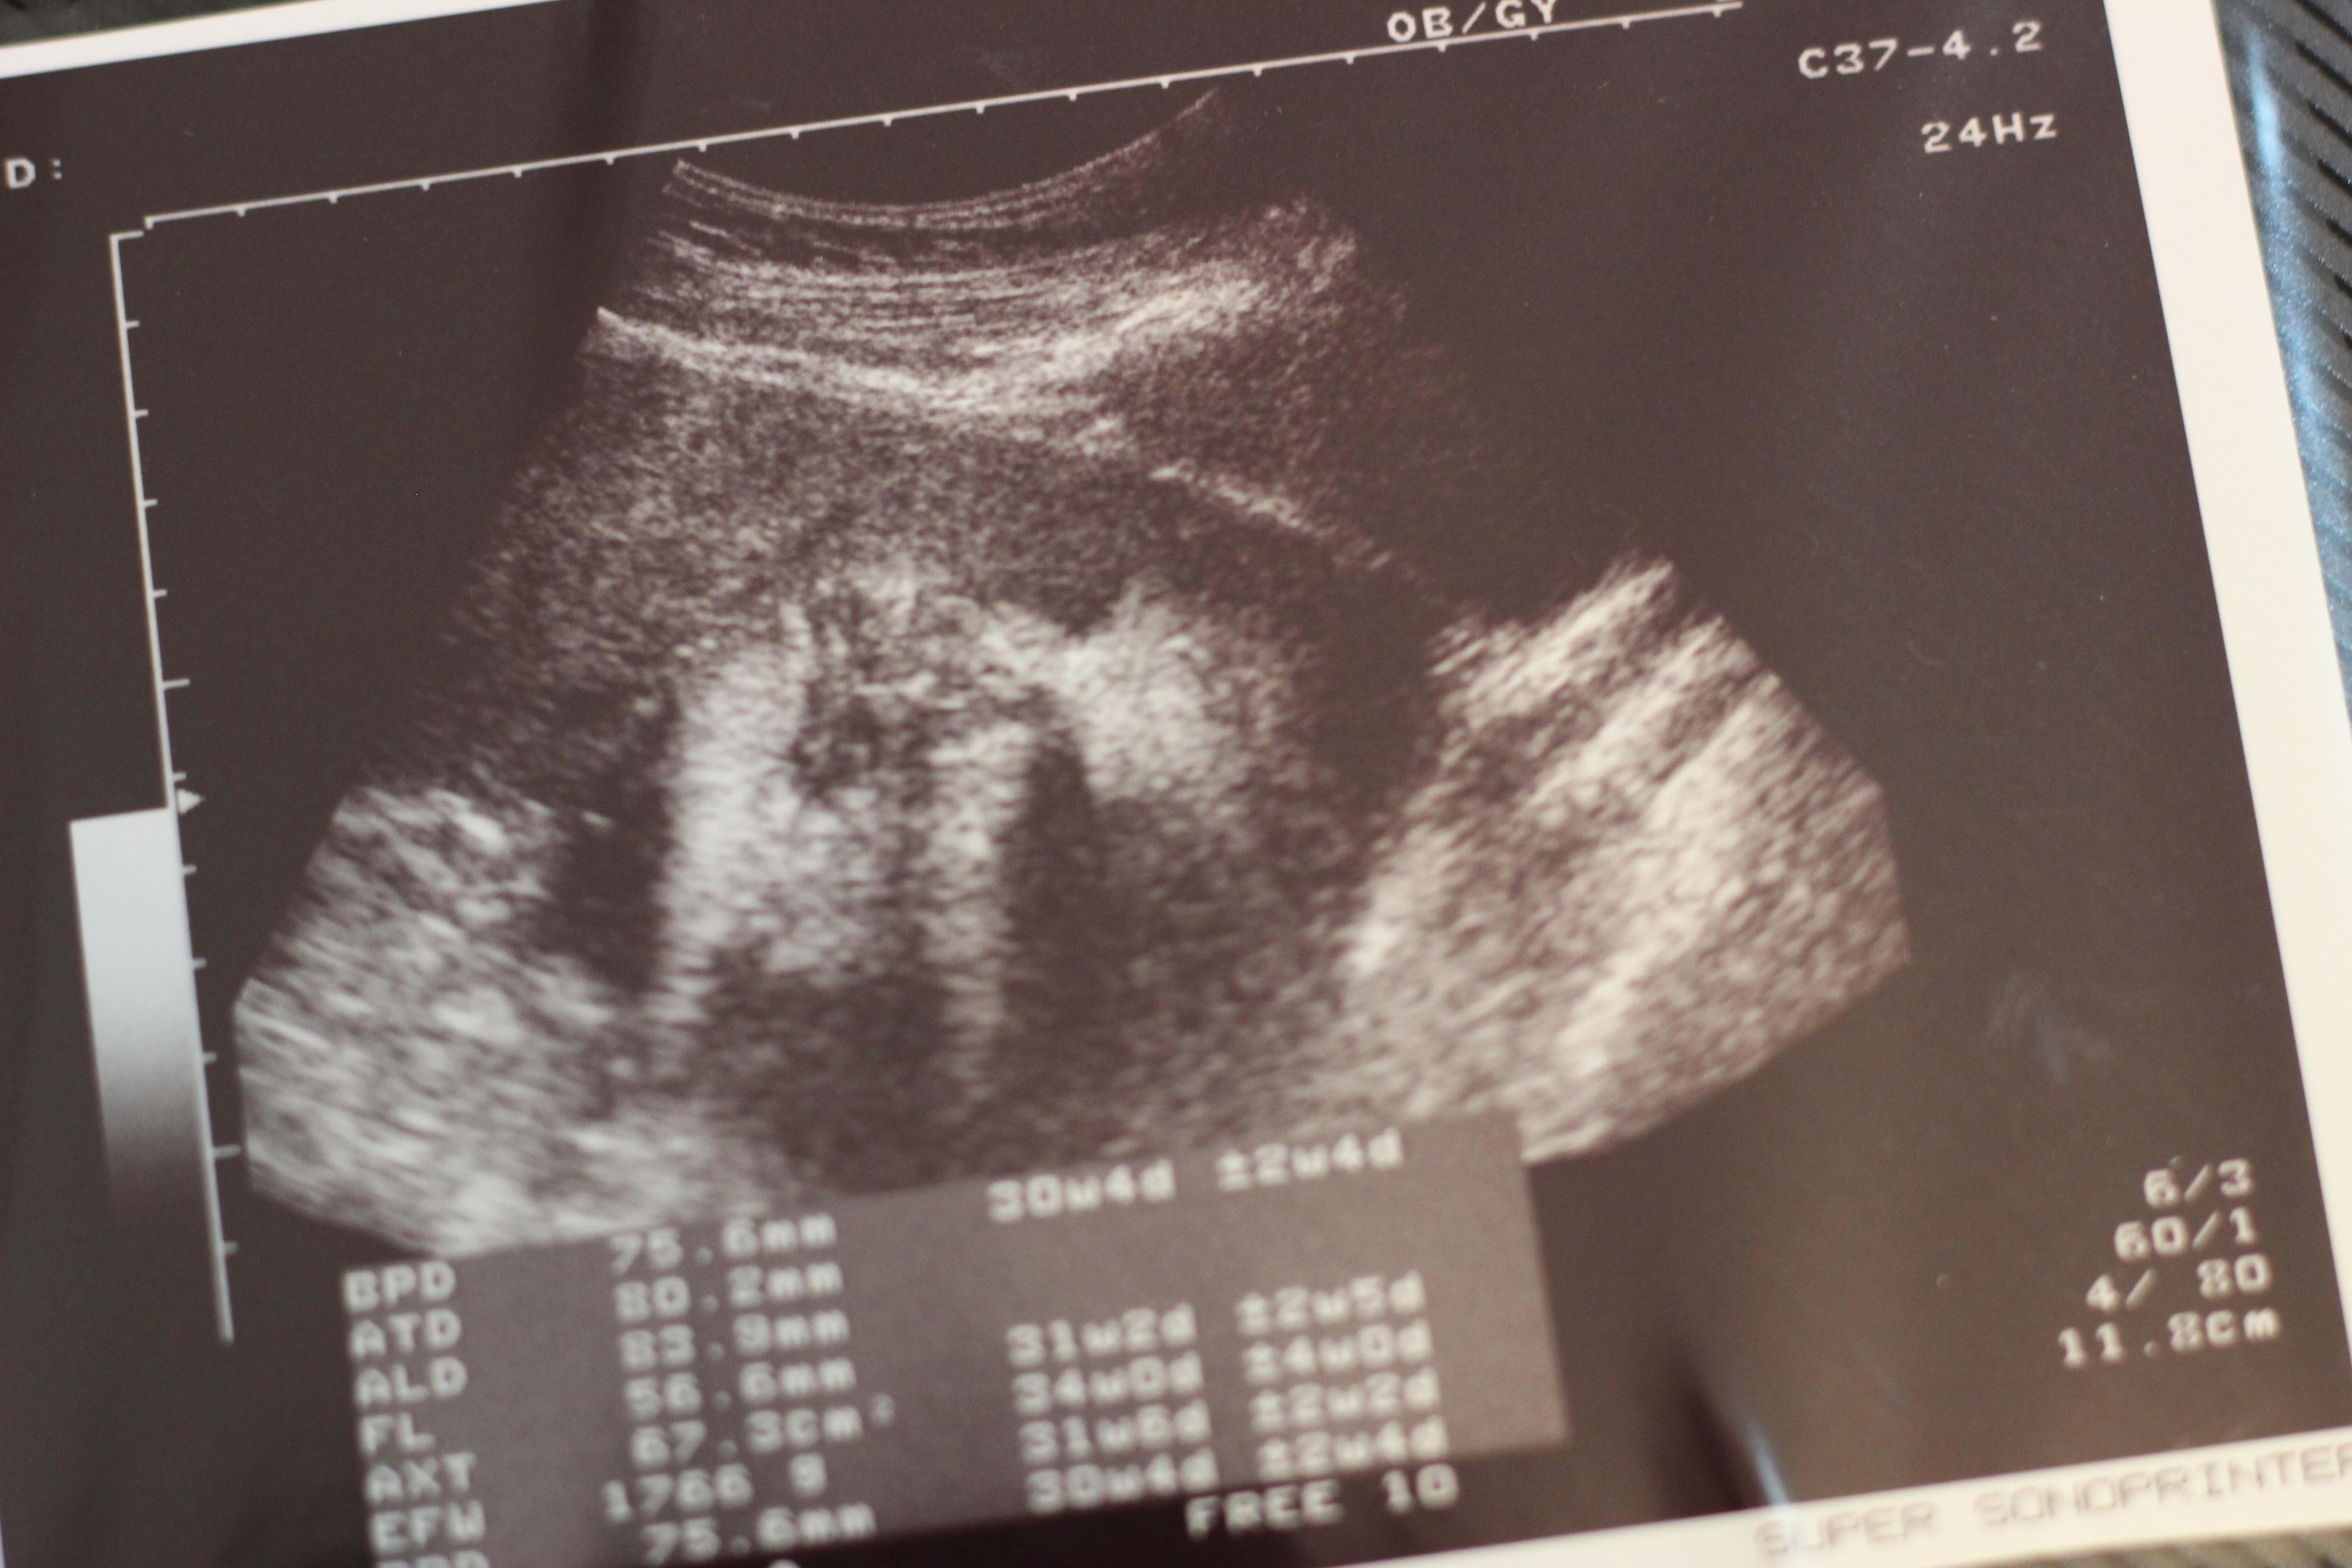

妊娠30週目のエコー写真

口をキュッとつぐむ様子も愛おしい表情。この頃は便秘がひどく、「酸化マグネシウム」を医師に処方してもらいました。この頃は安静にしながらも、週に1回催される母親学級へ車椅子で通い勉強していました。